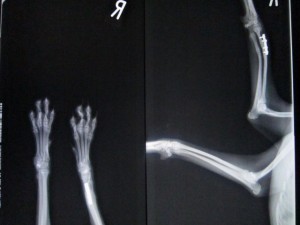

51日目のレントゲンです。

少しネジがゆるんでいますが、

骨癒合は良好です。